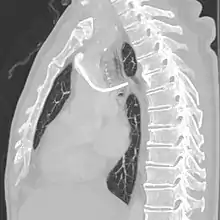

A follow-up on a chest radiograph can immediately detect complications associated with the procedure such as pneumothorax, hemothorax and malpositions of the catheter. However, routine chest radiography is not needed due to the low complication rates associated with the procedure. The chest radiograph is only done if there is clinical suspicion of a complication.[4]

The incidence of catheter fracture is 2.3%. The fracture can be due to "pinch-off syndrome" when the vein and the catheter is compressed when passes between the clavicle and first rib before turning 90 degrees into the superior vena cava. Fractured catheter component can dislodge most commonly into pulmonary arteries (35%), right atrium (27%), right ventricle (22%), and superior vena cava and peripheral veins (15.4%).[5]

Malpositioning of the catheter happens in 0.1 to 5.6% of the time. This can be due to malposition within or outside the superior vena cava. Causes includes: unexpected branches of the veins, vessel angulations, vein stenosis or venous tortousity.[5]

- Pneumothorax: Attempts to gain access to the subclavian vein or jugular vein can injure the lung, potentially causing a pneumothorax. If the pneumothorax is large enough, a chest tube might need to be placed. In experienced hands, the incidence of this complication is about 1% when accessing the subclavian vein. When accessing the jugular vein the pneumothorax rate is virtually nonexistent.